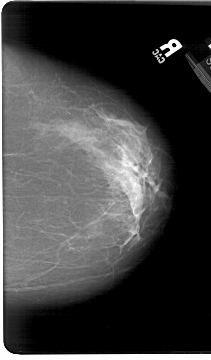

A_1386_1.RIGHT_CC

RIGHT_CC LINES 6826 PIXELS_PER_LINE 4006 BITS_PER_PIXEL 12 RESOLUTION 43.5 NON_OVERLAY